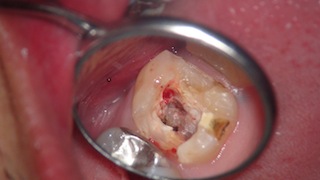

仮蓋を取り、虫歯が残っていたので除去したところ。

中も少し綺麗にしました。

隔壁を作ってから二回目の根管治療を行ったところです。

だいぶ綺麗になりました。

で、今回注目して欲しいのが、根管の数。

上の写真を見ると、根管の入り口が4つあるのがなんとなくわかるかと思います。